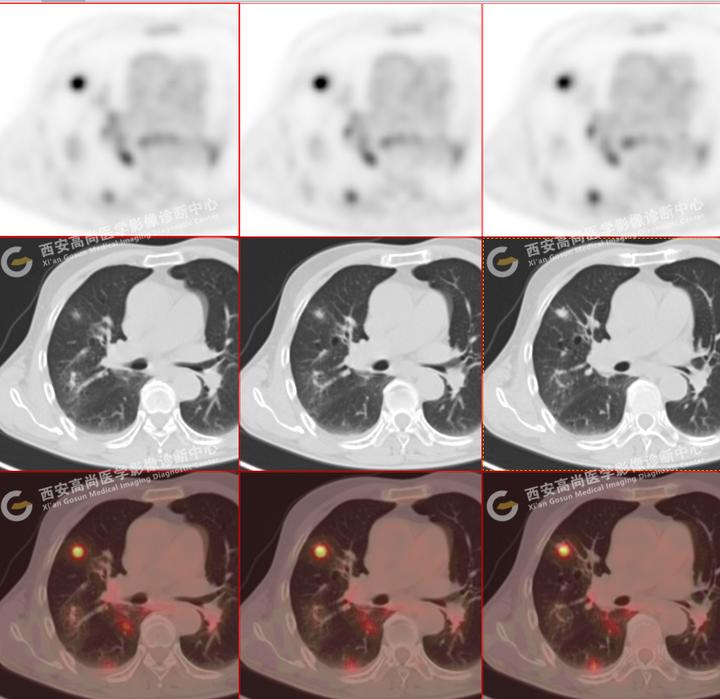

81岁男性,多发肺结节病例:重症感染 | 惠普尔养障体肺炎

图片尺寸720x699